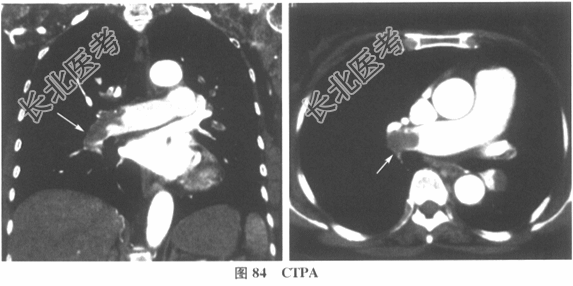

- 多项选择题2.[提示]患者血常规大致正常;血气分析(未吸氧): pH7.44,PaO258mmHg, PaCO229mmHg;心肌酶+TnT: 阴性;心电图如图83所示; 进一步完善CTPA检查,结果如图84所示。

根据以上辅助检查, 该患者目前的临床诊断为 A、Ⅰ型呼吸衰竭

G、急性肺栓塞